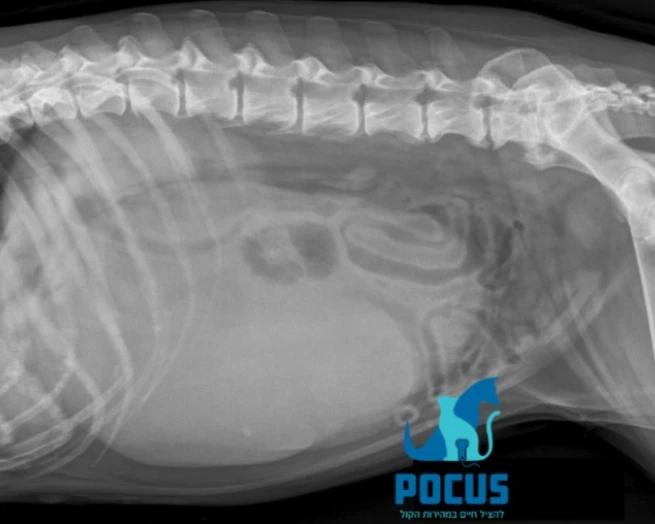

טחול - הדמייה בעזרת רנטגן ואולטרסאונד